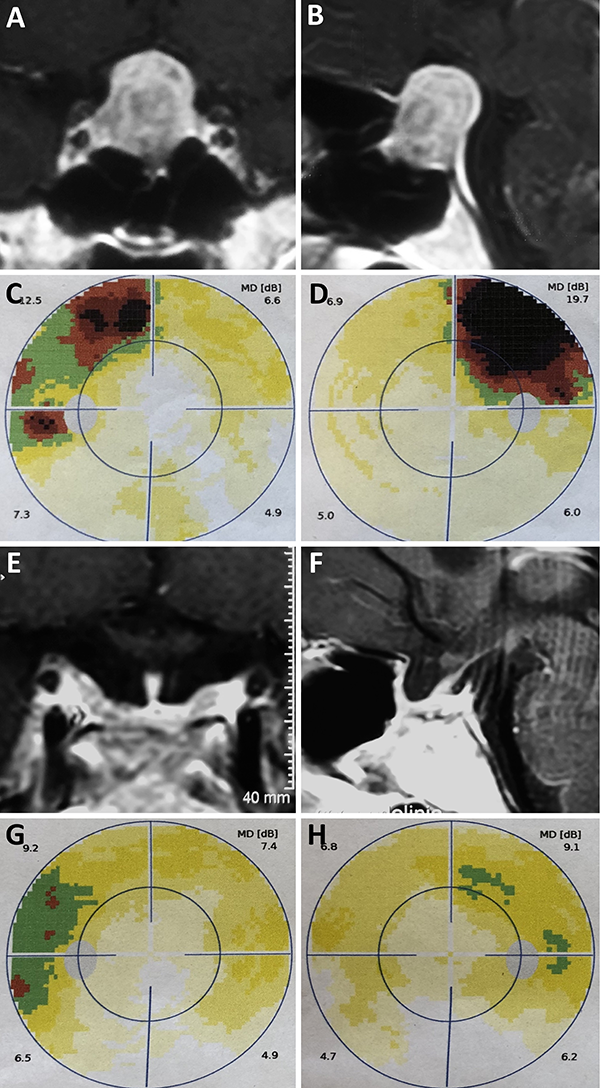

Una clasificación clásica de los adenomas es según su tamaño. Se los clasifica en microadenoma <10 mm (fig. 2), macroadenoma >10 mm (fig. 3), y adenoma gigante > 30 mm (fig. 4). Esta clasificación es importante ya que los índices de remisión están ligados al tamaño del adenoma y también su recidiva.12

Figura 2: Microadenoma. A-B: RM preoperatoria; C-D: RM postoperatoria.

Figura 3: Macroadenoma. A-B: RM preoperatoria; C-D: Campo visual preoperatorio; E-F: RM postoperatoria; G-H: Campo visual postoperatorio.

Figura 4: Adenoma gigante. A-B: RM preoperatoria; C-D: RM postoperatoria.